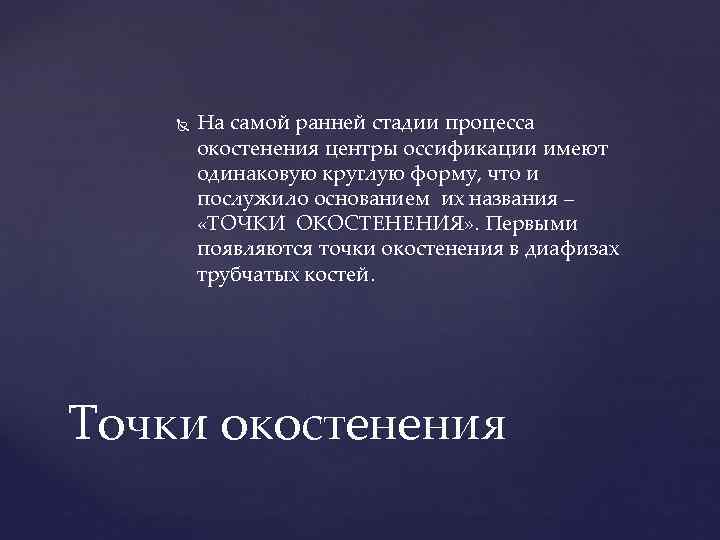

На самой ранней стадии процесса окостенения центры оссификации имеют одинаковую круглую форму, что и послужило основанием их названия – «ТОЧКИ ОКОСТЕНЕНИЯ» . Первыми появляются точки окостенения в диафизах трубчатых костей. Точки окостенения

На самой ранней стадии процесса окостенения центры оссификации имеют одинаковую круглую форму, что и послужило основанием их названия – «ТОЧКИ ОКОСТЕНЕНИЯ» . Первыми появляются точки окостенения в диафизах трубчатых костей. Точки окостенения